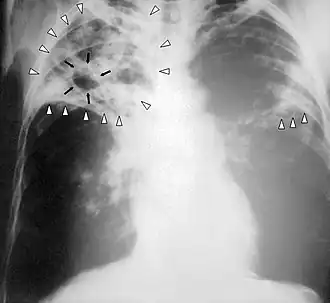

- Chest X-Ray - pericardial calcification (common but not specific), pleural effusions are common findings.[11]